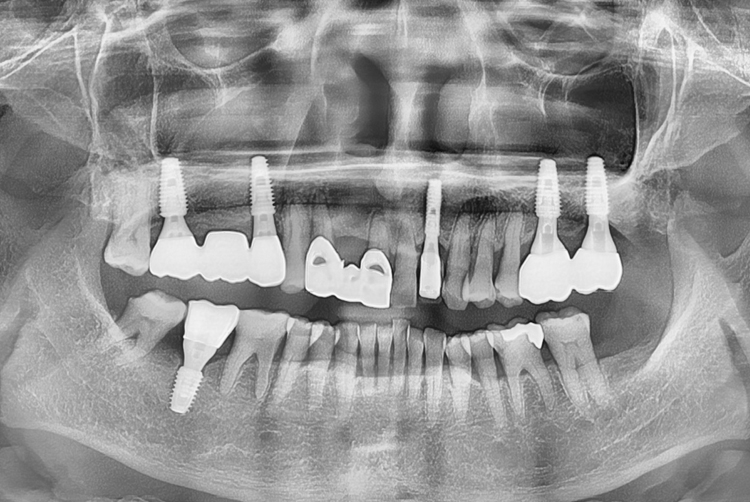

c948efc045347318d4e0e9af9c5a3737.jpg

치료전 : 2017-02-06

22.03.29.jpg

치료후 : 2022-03-29

세종치과는 많은 환자와 다양한 케이스를 바탕으로 항상 편안한 임플란트 수술을 제공하고자 노력하고,

오래동안 튼튼히 쓸 수 있는 임플란트 수술을 가장 큰 목표로 삼고 있습니다